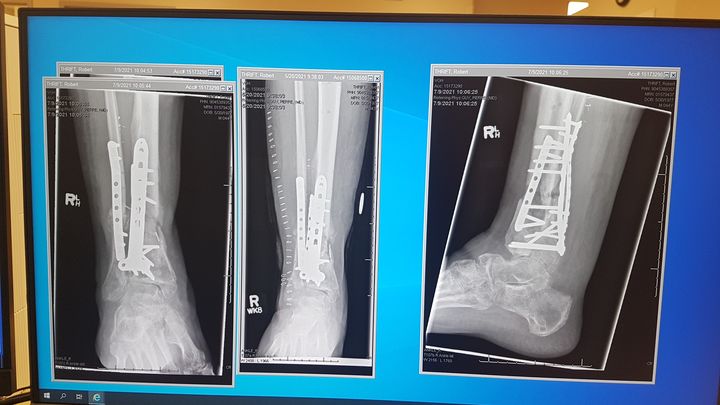

On July 10th 2020 I had a workplace accident that shattered my tibia and fibula on my right leg, effectively breaking it right off. After 2 surgeons and 5 surgeries I was able to keep my foot, but have been on Worksafe Benefits and unable to work for the last 2 years and counting.